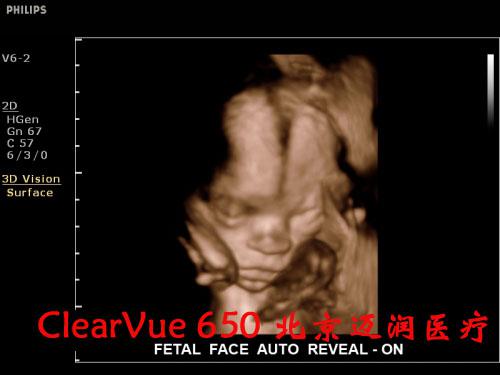

飛利浦ClearVue?CV650彩超

飛利浦ClearVue CV650(HD11XE升級版)是集成了飛利浦多項先進超聲技術(shù)的全身應(yīng)用型實時三維彩色超聲診斷系統(tǒng),采用了飛利浦最新的“元設(shè)計”理念。在原始信號的采集上,CV650飛利浦專利的超聲探頭微信號處理技術(shù)(雙A探頭技術(shù)),保證了零損耗寫真級實時數(shù)據(jù)采集,呈現(xiàn)更真實的圖像信息,可以大大減少臨床上的誤診與漏診的發(fā)生率。

良好的二維成像技術(shù)是保證實時三維圖像質(zhì)量的關(guān)鍵。CV650的實時三維成像融合了飛利浦傳統(tǒng)的優(yōu)勢技術(shù)SONOCT和Xres,保證了良好的圖像分辨力和對比度;另外,容積探頭也采用了“雙A探頭技術(shù)”,能夠?qū)崿F(xiàn)原始信號的零損耗,使呈現(xiàn)的三維圖像效果更逼真。同時,高速的處理內(nèi)核能使容積探頭實現(xiàn)最大48幁/秒的掃描速率,完成一次靜態(tài)掃描的時間也只需要2秒鐘,這些都保證了容積成像的可操作性。

在實時三維應(yīng)用上,CV650配備了胎兒面部自動識別軟件,全新的胎兒面部信息數(shù)字鑒定技術(shù),能夠一鍵清除遮擋物,使胎兒面部結(jié)構(gòu)尤其是異常缺陷能夠瞬間清晰顯示,大大便捷了醫(yī)生對胎兒面部的掃查過程。鑒于基層醫(yī)院對于胎兒心臟先天性疾病診斷能力的不足,這款機器還配備有STIC成像功能,簡單的操作、快速的圖像獲取、強大的離線分析能夠保證準確高效地獲取胎心不同標準切面,是基層超聲醫(yī)生診斷胎兒先心病的利器。

飛利浦ClearVue 650超聲系統(tǒng)臨床高清圖片